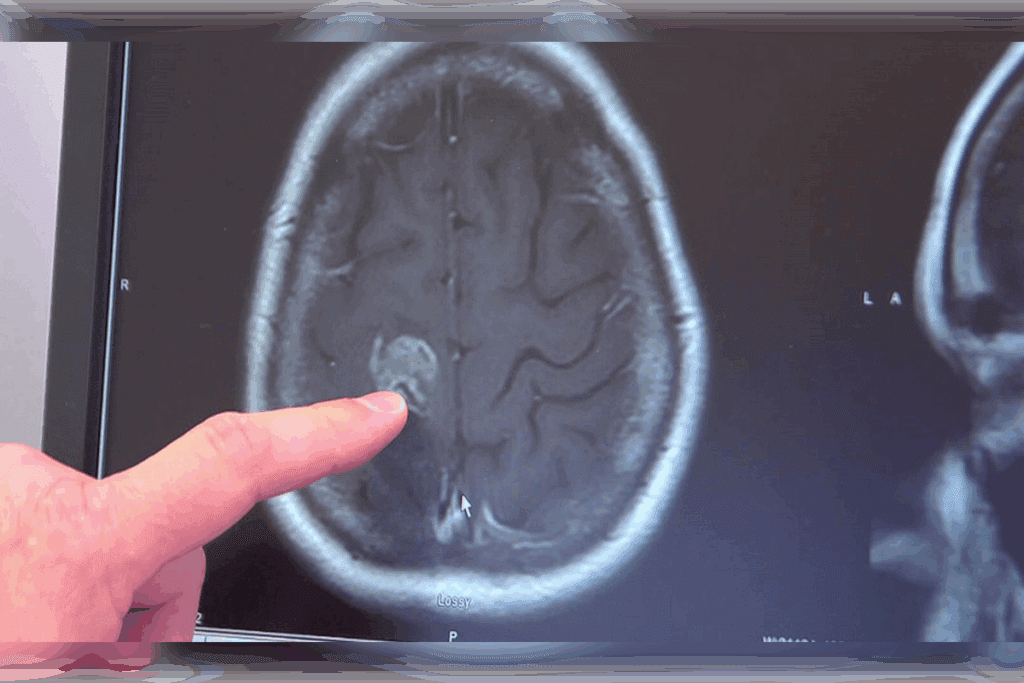

Advanced Imaging Techniques

Advanced imaging is vital for diagnosing brain tumors. Magnetic Resonance Imaging (MRI) is top choice because it’s sensitive and detailed, without radiation. It shows the tumor’s size and location.

Computed Tomography (CT) scans are used in emergencies. They’re quick but involve radiation and are less detailed than MRI.

| Imaging Modality | Advantages | Limitations |

| MRI | High sensitivity, detailed images, no radiation | Longer examination time, may require sedation |

| CT Scan | Quick, widely available | Involves radiation, less detailed than MRI |